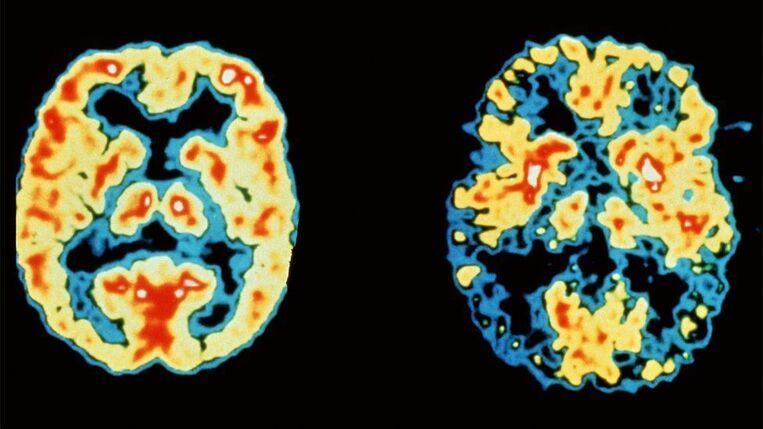

Πρόκειται για ένα μονοκλωνικό αντίσωμα, το οποίο στοχεύει στις αμυλοειδικές πλάκες που σχηματίζονται στον εγκέφαλο των ασθενών με νόσο Alzheimer.